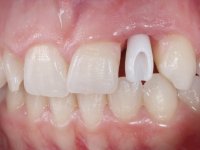

Before the treatment plan was elaborated, the patient was made aware of the inherent technical difficulty in aesthetical rehabilitation of the implant. After a long exchange of opinions with the dental technician, an unconventional treatment plan was presented, whose purpose was to minimize the aesthetic asymmetry between the left and right sides and between the cervical and incisal levels. The solution comprehended the realization of two veneers in composite resin of gingival tonality, to rehabilitate the interdental papillae of the edentulous space. A screwed abutment in Zr. with coronary and gingival component was planned for placement over the implant. As the implant angulation would put access to the screw on the vestibular face, confection of a feldspathic veneer was proposed, to be bonded to the abutment in order to camouflage the screw access hole. In tooth 1.2 a feldspathic veneer would be bonded, to correct microdontia and the small rotation.

An impression was made on the implant with open tray technique using soft and regular consistency putty. At the laboratory, after confection of the work model, a diagnostic waxing was performed, which sought to find an aesthetic compromise solution. In this sense, a temporary workpiece screwed onto the implant was used to simulate the difficulties we would have with screwing the definitive work. This study abutment consisted of wax to reproduce soft and hard tissues, seeking to anticipate the use of ceramics of gingival and coronary shade. Also, part of the interproximal papillae corresponding to the distal portion of the 2.1 tooth and the mesial tooth of the tooth 2.3 were also waxed, anticipating the use of composite resin “chips” with gingival tonality. Finally, a veneer was waxed to correct the microdontia of the tooth 1.2. In this waxing, the vestibular emergence of the orifice for access to the screw of the implant abutment was evident. Once this therapeutic option was accepted, the implant abutment in polymerized composite resin was prepared at the lab, as well as the papillary "chips", also in composite resin of gingival tonality. Tested in the mouth, the abutment was screwed and the "chips" bonded. The access hole of the screw was filled with composite resin. In subsequent consultation, a gingivectomy was performed on the cervical contour of teeth 1.3, 1.2 and 1.1 with the aim of correcting the asymmetry between the first and second quadrant. After the soft tissues were cicatrized, a dental bleaching was performed according to the patient’s aesthetic requirements. Final impression on the implant was made using the silicone open tray technique, taking care to individualize the transfer piece by copying the emergence profile of the patient’s provisional abutment. At the laboratory, the impression yielded a definitive working model, on which the abutment was waxed on a plastic insert. This process was carried out with the orientation of a wall of silicone based on diagnostic waxing. The wax made on the plastic part was placed in a special holder that allowed its scanning in a laboratory scanner. This scan by CAD process informed the design of an abutment in Zr. later materialized by a CAM process. The Zr. abutment was tested in the mouth, validating its clinical and imaging establishment. During this consultation, the choice of color was made by the ceramist, of both the coronary ceramics and the ceramic of gingival tonality to be used. Individualized color scales were used. At the laboratory, the coronary and gingival ceramics were placed on the implant abutment and later, on a working model with refractory gypsum, a veneer of feldspathic ceramic was made. This veneer was built on a surface specially designed for this purpose in the abutment. This surface tried to reproduce a dental preparation performed for the same effect. In the mouth the abutment was screwed with a torque of 35N, the access hole to the screw was filled with Teflon and later filled with composite resin. The veneer was bonded onto the implant abutment using the conventional bonding technique, with relative insulation. For economic reasons, the patient did not proceed to perform the veneer on tooth 1.2. Although a limited aesthetic compromise was expected from the outset, a result was achieved which satisfied the patient.